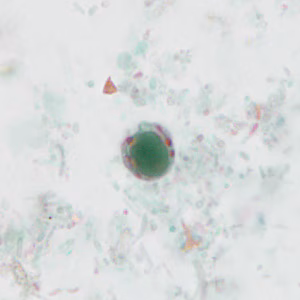

Stool specimens were collected from an asymptomatic 10-year-old boy from Panama as part of a refugee screening program. The stool was collected in 10% formalin and zinc PVA (Zn-PVA) and sent to the county health department for routine ova-and-parasite (O&P) examination. Figures A – I show what was observed at 1000x magnification with oil on a trichrome-stained slide made from stool preserved in Zn-PVA. Objects in Figures A and G measured approximately 10 micrometers; all other objects of interest ranged from 17-25 micrometers. Figures C – E show different focal planes of the same object of interest to highlight internal structures. What is your diagnosis? Based on what criteria?

Figure A